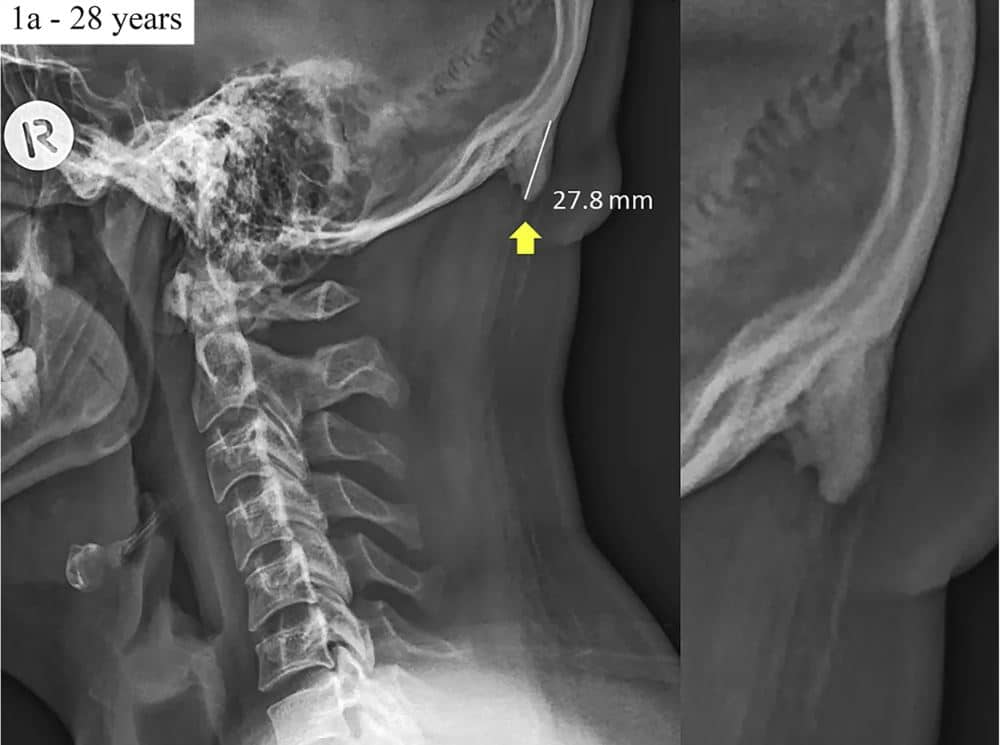

Uno studio apparso sulla rivista Scientific Reports rivela come il nostro cranio stia subendo delle modifiche proprio per colpa degli smartphone. Le “corna”, appunto, sarebbero dei piccoli corni ossei nella parte posteriore del cranio registrati dagli studiosi nella parte posteriore del cranio.

Queste “corna” nascono a causa della posizione assunta quando si ha in mano uno smartphone e si osserva lo schermo. La testa inclinata in avanti farebbe sì che il peso della colonna vertebrale sia caricato tutto nella parte posteriore della testa. Da qui la crescita ossea nella parte posteriore del cranio.

A studiare il fenomeno è l’Università australiana della Sunshine Coast, secondo cui questi picchi a forma di cono si presenterebbero maggiormente nei giovani, a causa dell’uso sconsiderato degli smartphone.

218 i soggetti coinvolti nello studio, tutti tra i 18 e i 30 anni. Secondo l’analisi condotta dagli studiosi, il 41 per cento ha sviluppato le “corna” di una lunghezza tra i dieci e i 30 millimetri.